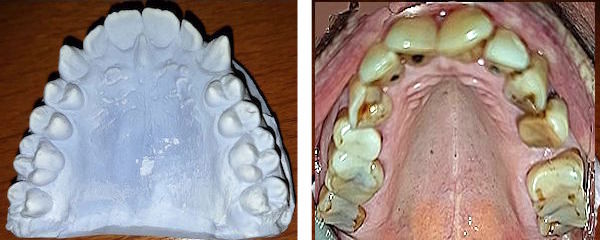

Die Zunahme der Anzahl Zähne

Die Jahrgänge 1910-1930 hatten etwa 9 Zähne pro Kiefer. Die Prothesen, Teilprothesen und Zahnlücken

schränkten den Bruxismus ein.

Bis 1960 stieg dank der Schulzahnpflege die Zahl der Zähne auf 12 pro Kiefer.

Seither bleiben fast bei jedem 14 und mehr Zähne gesund.

Auf solchen lässt sich bis ins hohe Alter stets kraftvoll knirschen.

Die Zunahme des Alters der Zähne verlängert die mechanische Belastung durch den Bruxismus. Das Alter der Patienten hat in den letzten 35 Jahre volle 20 Jahre zugenommen (siehe hier). Interessanterweise bleibt der Stress auch im Alter erhalten. Zum Beispiel kann ein stark belasteter Zahn schliesslich abbrechen. Oder es beginnt ein Zahn zu schmerzen, weil der Nachbarzahn verloren gegangen ist. Oder die Zähne nützen sich so weit ab, dass plötzlich mehrere Füllungen nötig werden. Während solche Zähne früher oft mit Prothesen ersetzt wurden, mit denen man nicht knirschen kann, werden sie heute meisens ersetzt und setzt sich der Bruxismus fort.